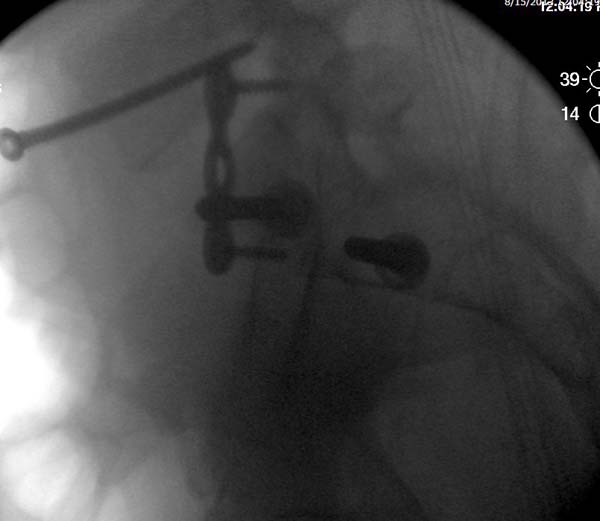

Перелом заднего отдела крыла подвдошной кости доказывает, что задние

связочные элементы подвздошно- крестцового сочленения интактны, и такой

перелом известен как“Сrescent fracture’. Переломы разделяется на 4 типа,

и до фиксации надо хорошо изучить топографию перелома, иначе винт может

попасть в линию перелома и не удержать фиксацию.

Но вам повезло, двумя винтами смогли зацепить и репонировать

переломо-вывих. Обычно такие переломы надо фиксировать спереди или сзади

пластиной или шурупом, т.е. создать дополнительную стабильность крыла,

кроме  перкутанной фиксации.

Здесь примеры фиксации с различными вариантами.... .